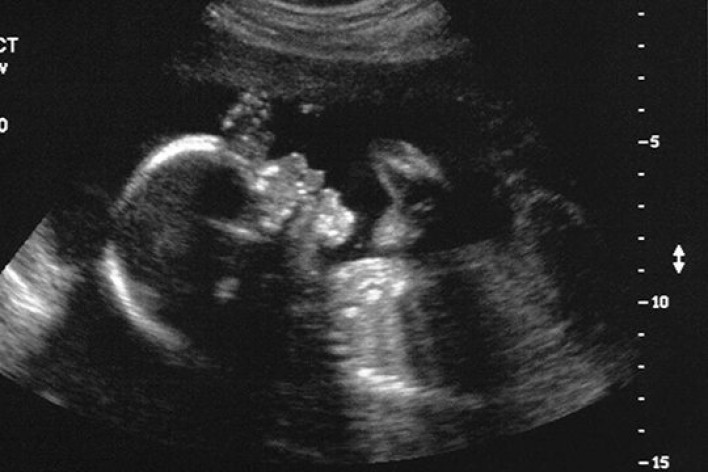

Աննախադեպ.3 ծնողների երեխա կծնվի

New Scientistամսագիրը հայտնում է,որ  Մեծ Բրիտանիայի կարգավորող մարմինները հաստատել են 3 ծնողների երեխաների բեղմնավորման 2 փորձ: Մեթոդը մշակել է ղազախ-ամերիկացի կենսաբան Շուքրաթ Միթալիփովը: Փորձագետները սպասում են, որ 3 ծնողների առաջին երեխաները կարող են ծնվել Մեծ Բրիտանիայում արդեն 2018 թ.: Գիտնականները հանում են բեղմնավորված ձվաբջջի միջուկը և այն տեղափոխում են դոնորական ձվաբջջի մեջ, որի միջուկը նախապես հեռացվում է: Հետո այն փոխպատվաստում են իրական կամ փոխնակ մոր արգանդի մեջ: